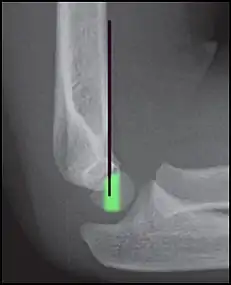

Anterior humeral line - It is a line drawn down along the front of the humerus on the lateral view and it should pass through the middle third of the capitulum of the humerus.[9] If it passes through the anterior third of the capitulum, it indicates the posterior displacement of distal fragment.[8]

Anterior humeral line (black line), with normal area passed on the capitulum of the humerus colored in green in a 4 year old child.[9]

The anterior humeral line is not reliable in children with sparse ossification of the capitulum, such as in this 6 months old child.[9]